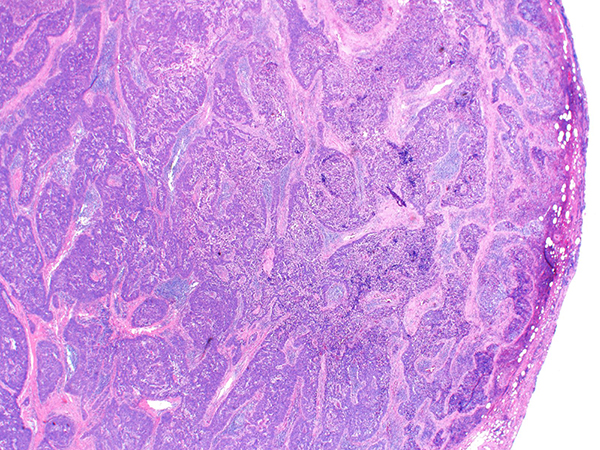

Clinical History: A 60-year-old man with no significant past medical history, presented with several months of weight loss and fatigue. A chest CT revealed a 4 cm anterior mediastinal mass. The patient underwent resection of the mass. H&E images are shown in Figures 1-4. Results of immunohistochemical stains are in Figures 5 and 6.

Thymic squamous cell carcinoma shows morphologic features similar to those of squamous cell carcinoma in other organs. Unlike thymoma, it often lacks a lobular architecture. Thymic squamous cell carcinoma accounts for the majority (~70%) of thymic epithelial malignant neoplasms and mostly occurs in the sixth decade. Males and females are almost equally affected. The etiology is unknown and there is no association with environmental factors, including cigarette smoking. About 1/3 of patients are asymptomatic at the time of presentation but others may have chest pain, cough and shortness of breath due to mediastinal compression. Paraneoplastic syndromes have been rarely reported. On imaging, TSCCs present as an anterior mediastinal mass and tend to have irregular borders with central areas of necrosis or cystic change. Tumors may invade the surrounding mediastinal structures, including the pericardium, lung, pleura, and major vessels. Regional lymph node and distant metastases are not uncommon.

Grossly, the tumors range in size from 2-17 cm (mean 7 cm) and lack the encapsulation or internal fibrous septation seen in thymomas. Frequent foci of necrosis and hemorrhage may be seen. Histologically, the tumor is composed of sheets, nests, and cords of tumor cells with vesicular to hyperchromatic chromatin and distinct nucleoli (Figures 1-3) with associated chronic inflammation and desmoplastic stroma (Figure 4). Unlike thymoma, the intermixed lymphocytes are mature T cells and B cells. Terminal deoxynucleotidyl transferase (TdT)-positive immature T lymphocytes are absent (Figure 6). Tumor nests often have a smooth contour (Figure 2) but areas of infiltration with irregular borders are also found (Figure 4). By immunohistochemistry, thymic squamous cell carcinomas are immunoreactive for keratins, and most are positive for PAX-8 and p40 (Figure 5). Additional markers such as CD5, CD117 (Figure 5), GLUT1 and MUC1 are frequently expressed in thymic carcinomas, but are much less common in thymomas, and therefore may potentially be of value in the differential diagnosis of difficult cases. Focal expression of neuroendocrine markers is common in thymic carcinomas, but is rare in thymomas. The differential diagnosis also includes pulmonary squamous cell carcinoma, and therefore clinical and radiological correlation as well as CD5 and CD117 markers help in distinguishing thymic squamous cell carcinoma from pulmonary squamous cell carcinoma.

Take home message: Thymic squamous cell carcinoma can be distinguished from type B3 thymoma by its infiltrative growth pattern, foci of necrosis, increased cytologic atypia, lack of TdT-positive lymphocytes and expression of CD5, CD117, GLUT1 and MUC1.